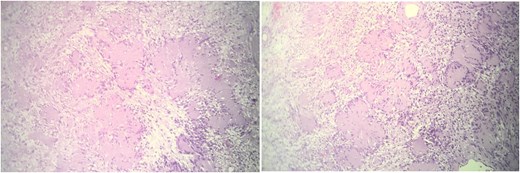

Histopathological examination revealed a well-circumscribed encapsulated tumor with a biphasic pattern, comprising hypercellular Antoni A areas and hypocellular Antoni B areas. Nuclear palisading and Verocay bodies were identified, along with degenerative nuclear atypia and cystic changes consistent with the diagnosis of an ancient schwannoma. No evidence of malignancy was found (Fig. 3).

These histological images demonstrate a well-circumscribed tumor with distinct biphasic architecture, characteristic of schwannomas. The hypercellular Antoni A areas, marked by closely packed spindle cells arranged in a palisading pattern, are interspersed with hypocellular Antoni B regions, which exhibit loosely arranged spindle cells within a myxoid stroma. Additionally, degenerative changes, including cystic spaces and evidence of hyalinization, are evident, aligning with the features of an ancient schwannoma. The absence of mitotic figures or necrosis suggests the benign nature of the lesion. This histological presentation, combined with clinical and imaging findings, confirms the diagnosis of an ancient schwannoma.

Retroperitoneal schwannoma is a solid, encapsulated benign tumor that typically originates in the paravertebral region. On gross examination, it presents as a solitary, well-defined mass with a smooth surface. Histologically, schwannoma is composed of Schwann cells displaying alternating hypercellular (Antoni A) and hypocellular (Antoni B) areas, and it demonstrates positive staining for S100 protein. The presence of degenerative features, such as cystic changes, hemorrhage, calcification, and hyalinization, characterizes a specific subtype known as ancient retroperitoneal schwannoma [2].